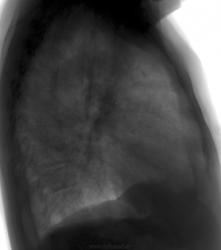

2. Пациент С.,1934. Находится сейчас в кардиологии. Направлен на ЦФГ с Дз: плеврит. Выполнены снимки. Предыдущая ЦФГ от 06.11.09( смотрела не я). Как рассказал сам пациент зимой был эпизод кровохарканья, никуда не обращался.

Снимки от 24.03.10

Снимок от 06.11.09

Снимок от 06.11.09

2.Сердце к первому снимку увеличилось в обьеме.в прикорневых эонах усилен сосудистый рисунок,в плевральной полости справа жидкость.р-я паракостальной плевры,возможен затек по междолевой плевре.(жидкость сердечного генеза)кровохарканье возможно.На верхушке справа кальцинат.

Второй случай - Что за округлая тень в S6 справа, может здесь переферический рак, с метастатическим плевритом?

2. Согласен с Еленой. Прогресс кардиодилятации в динамике, полнокровие МККО, транссудат, пардон, гидроторакс справа с элементом междолевого скопления.